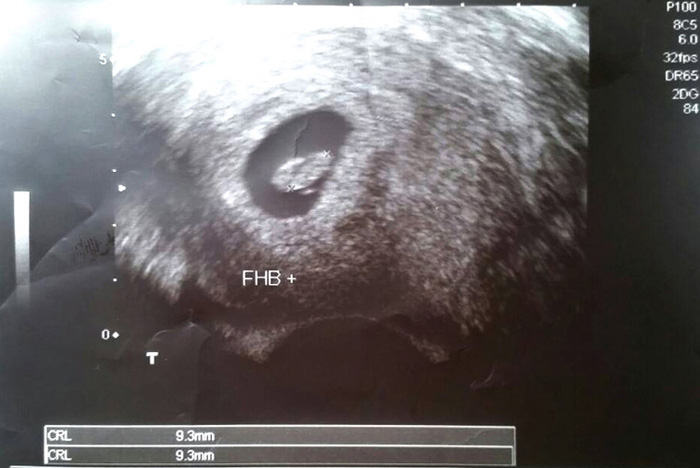

今天是懷孕八週,一切應該都很正常

終於在第九周聽到小泥巴的心跳,非常的快速,連老公也都露出開心的眼神

小泥巴已經有3.5公分大小,心跳頻率也很正常

醫生檢查後,小泥巴已經6公分大了